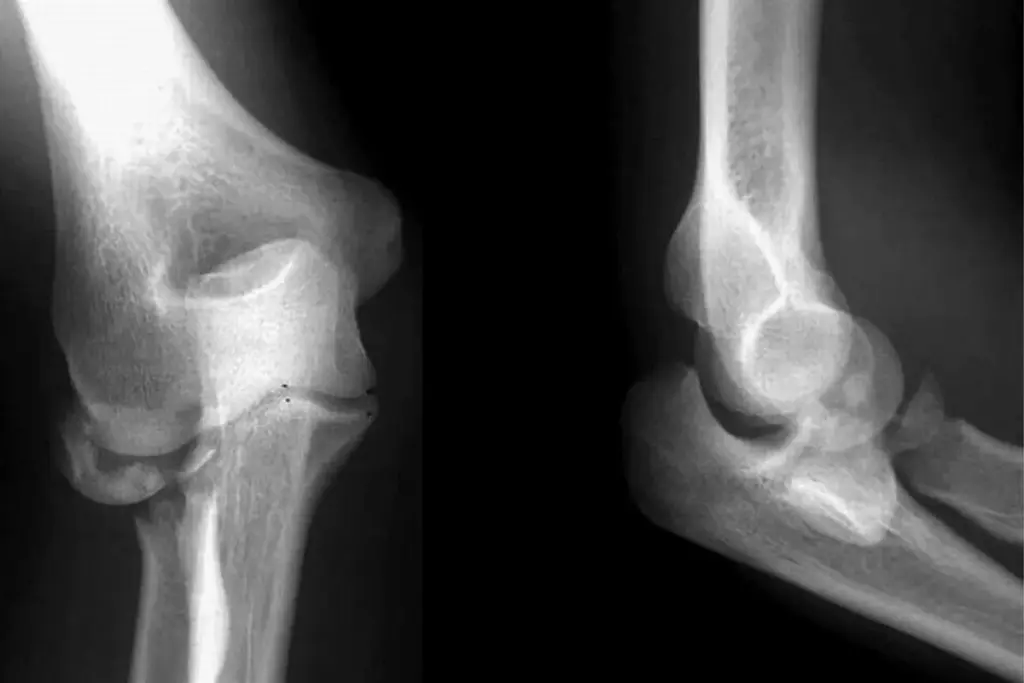

Diagnosing a CFL strain needs a detailed history and physical check. We use tests like the talar tilt test to check the CFL. X-rays and MRI help confirm the diagnosis and rule out other injuries.

The Ottawa ankle rules help decide if an X-ray is needed. An X-ray is suggested if there’s pain in the malleolar zone and any of these: age 55 or older, can’t bear weight right away, or tenderness in certain areas.